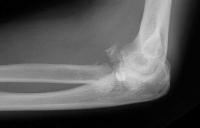

Initial reduction, elsewhere.

Click for larger image